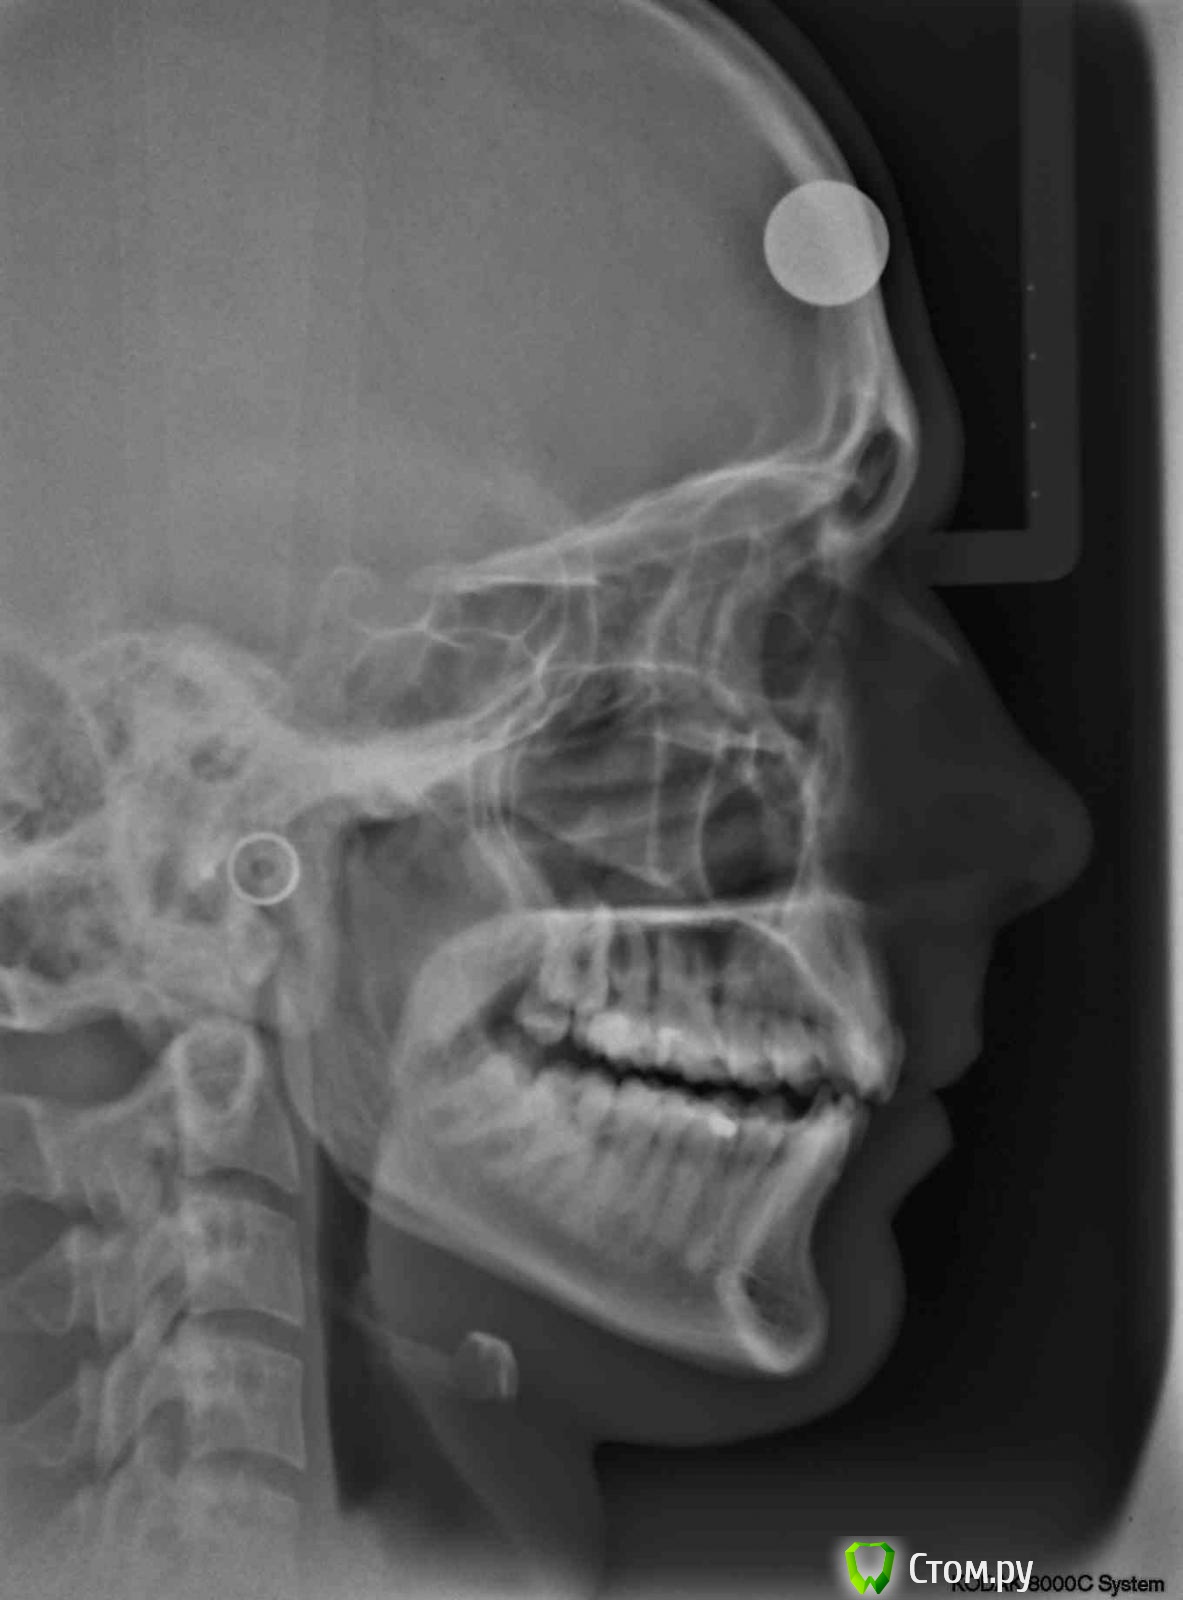

Татьяна_200 Опубликовано 17 августа, 2014 Поделиться Опубликовано 17 августа, 2014 Здравствуйте, планирую установить брекеты . Консультировались у ортодонтов, кто-то рекомендует удалить восьмерки перед лечением.Один врач сказал, что можно их удалить в любой момент, а сейчас будет ставить без удаления. Очень срочно нужен совет , нужно ли удалить их перед лечением или можно будет в любое время, даже после снятия брекетов? Ссылка на комментарий

samsonov Опубликовано 17 августа, 2014 Поделиться Опубликовано 17 августа, 2014 Нижние, имхо, актуальнее удалить раньше, их локализация создаёт предпосылки скученности и воспаления, однако в правильных руках можно все три сразу убрать и заморачиваться.) 1 Ссылка на комментарий

Татьяна_200 Опубликовано 20 августа, 2014 Автор Поделиться Опубликовано 20 августа, 2014 Спасибо за ответы. Понятно, что удалять нижние нужно в любом случае, но можно ли оставить верхние восьмерки? Влияют ли они на ближайшие зубы? Ссылка на комментарий